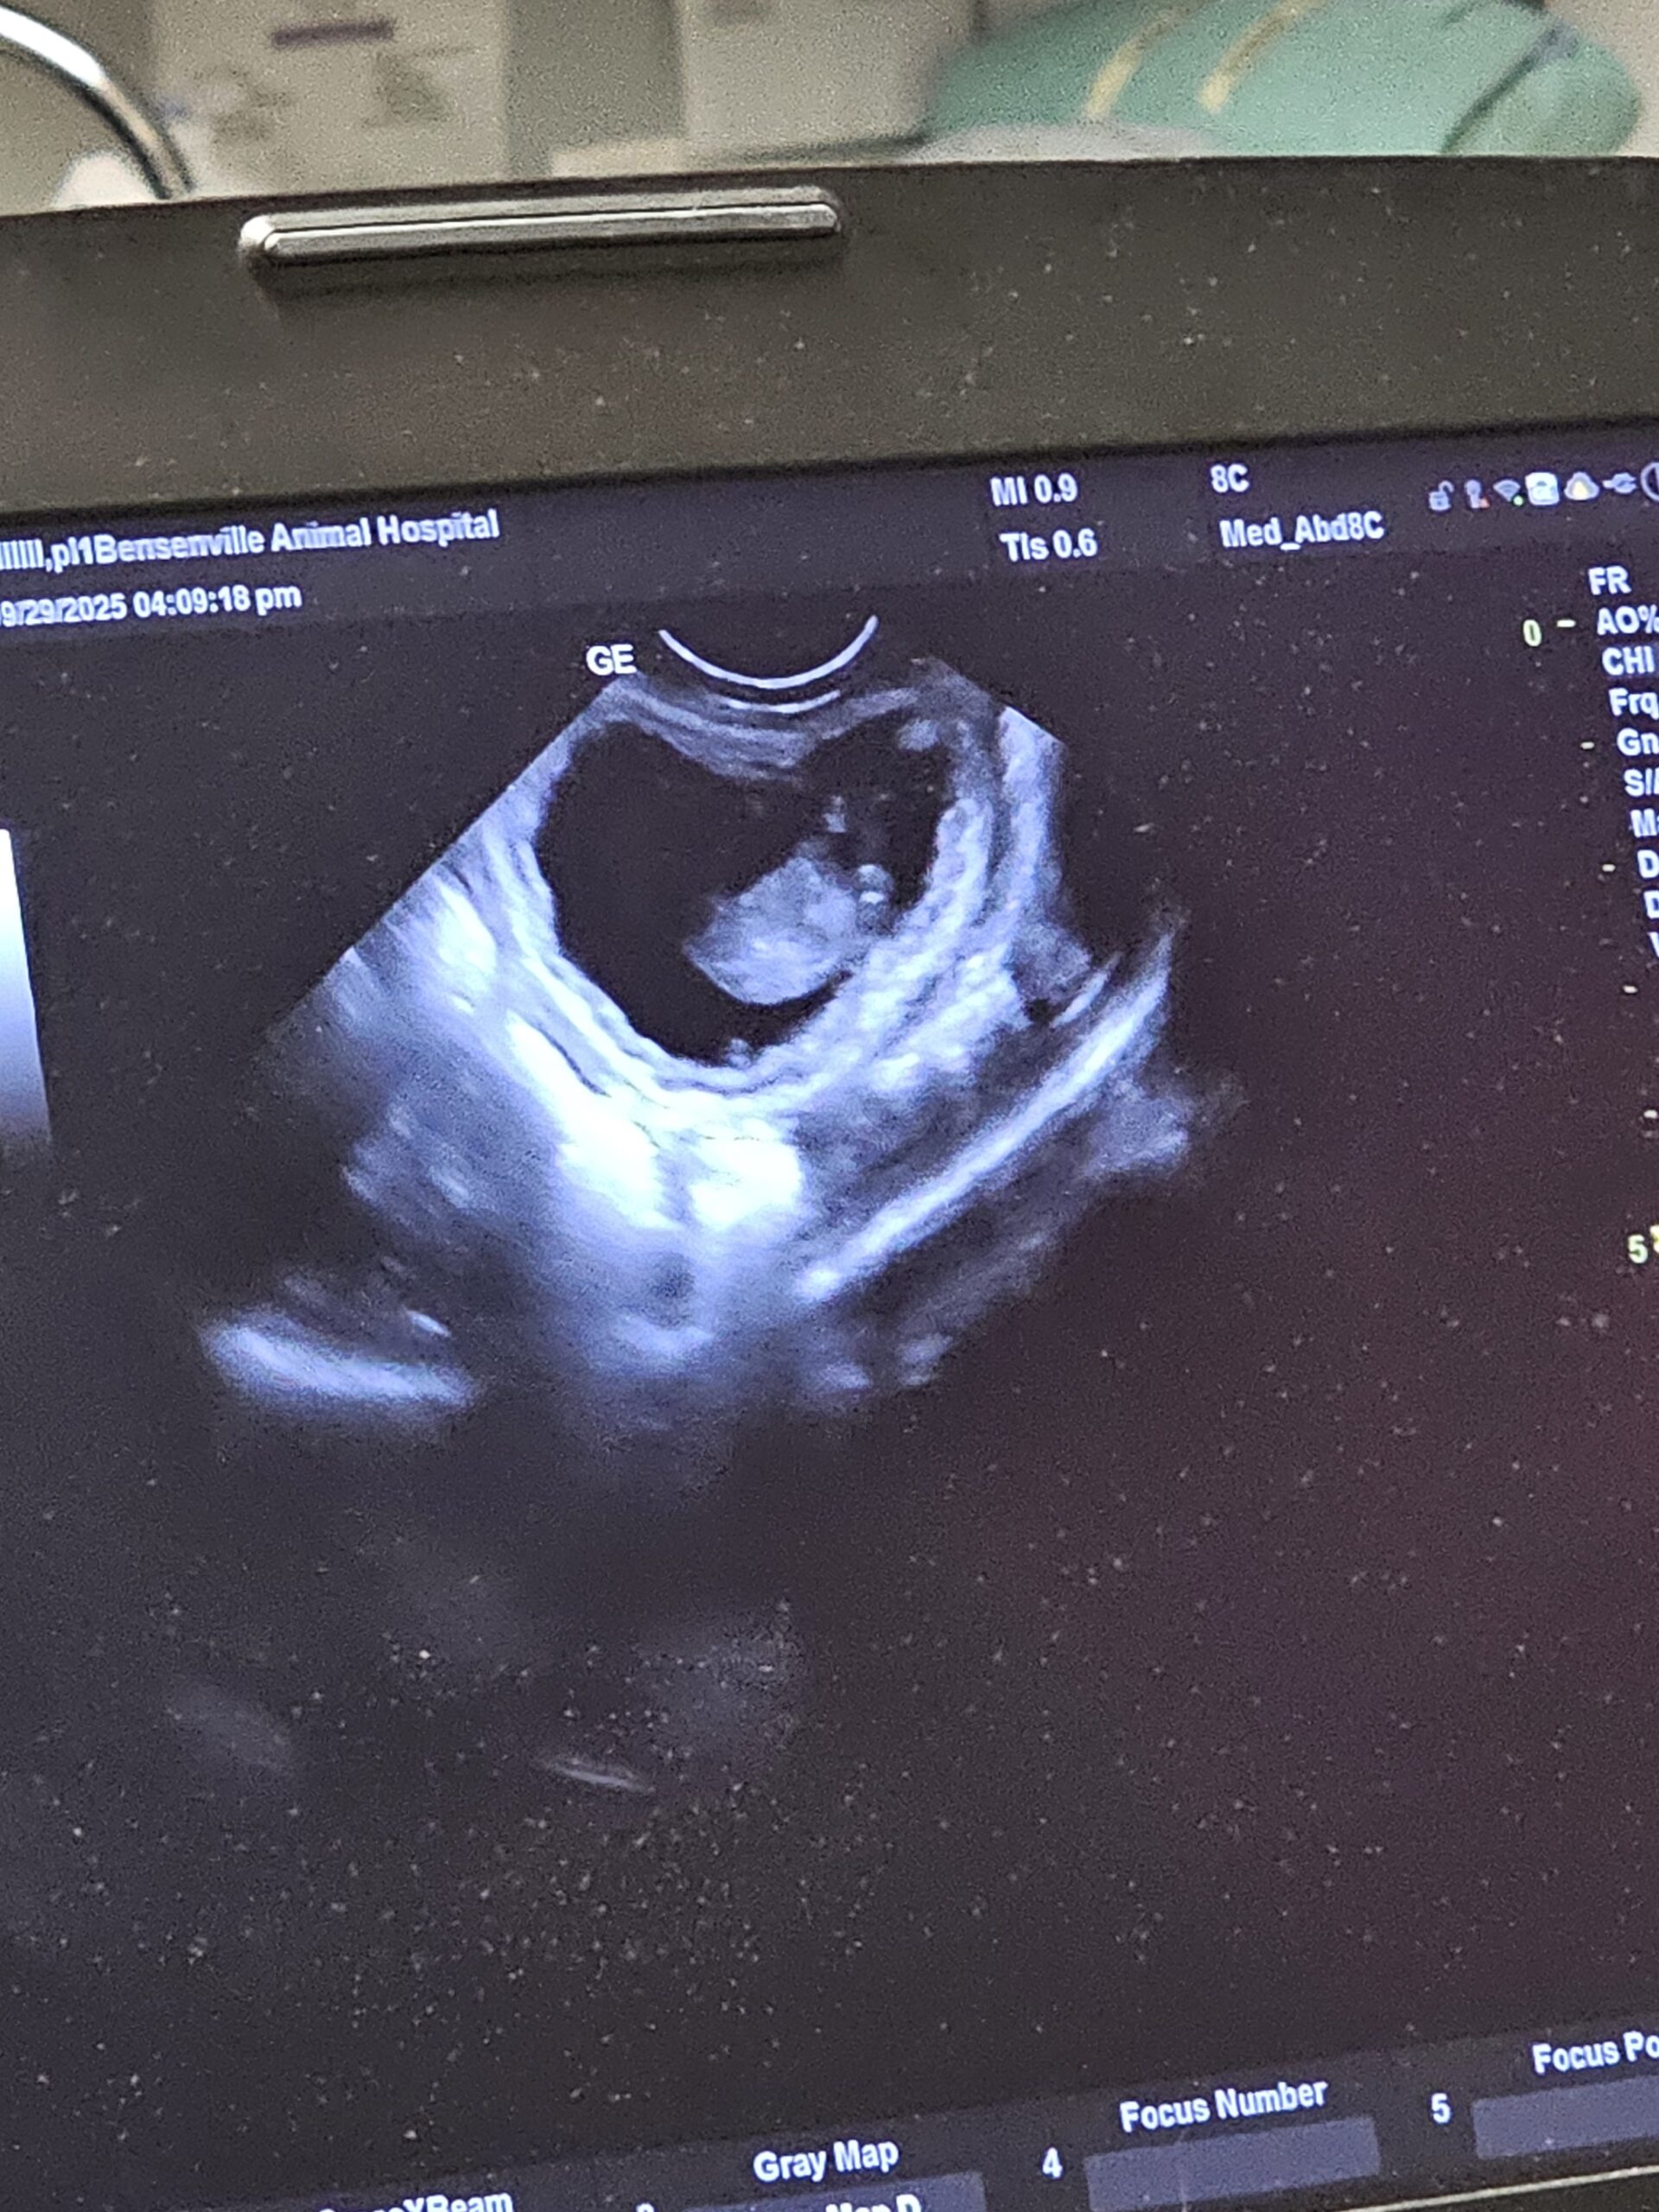

Ultrasound is a safe, non-invasive imaging tool that allows our veterinarians to see what’s happening inside your pet’s body in real time, without the need for surgery or radiation. Using sound waves, we can visualize your pet’s organs and soft tissues, helping us detect and diagnose conditions involving the liver, kidneys, bladder, heart, spleen, and reproductive system, as well as identify masses, fluid buildup, or foreign objects.